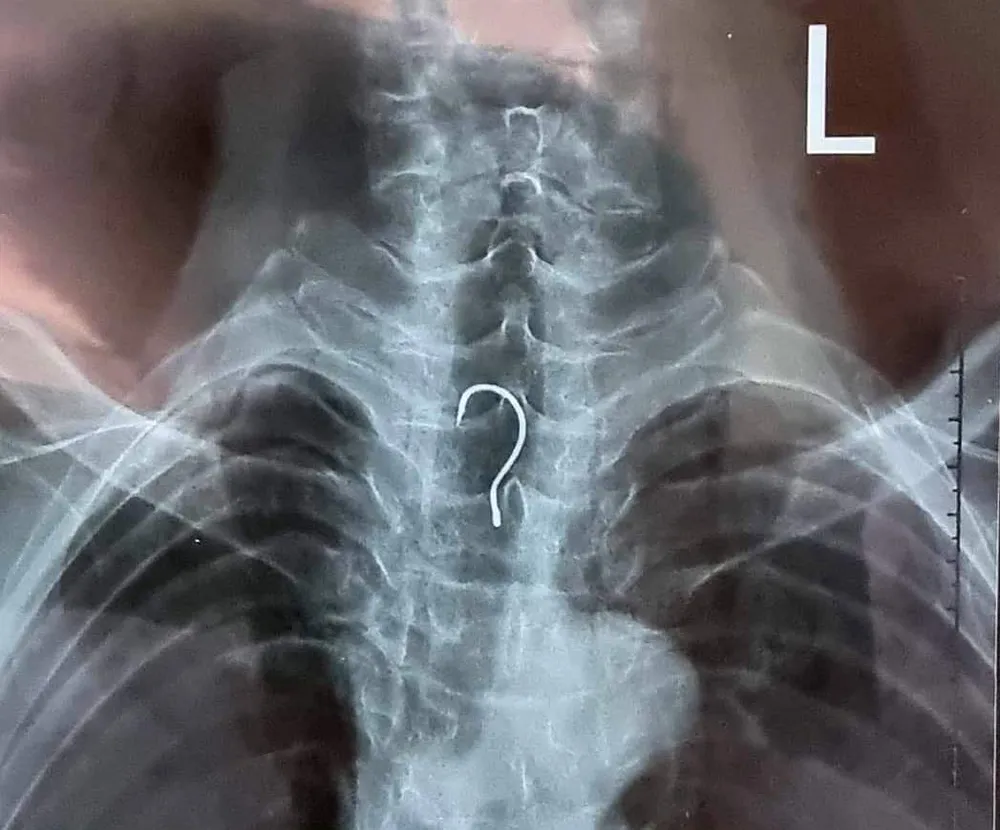

Sau khi được đưa vào bệnh viện, bệnh nhân T.V.A. đã nhanh chóng được các bác sĩ cho chụp phim X-quang và chỉ định nội soi thực quản - dạ dày - tá tràng không sinh thiết.

Kết quả, qua nội soi, các bác sĩ phát hiện dị vật nằm ở trong khu vực thực quản của bệnh nhân. Ngay sau đó, ê-kíp nội soi đã gắp ra ngoài dị vật là một chiếc lưỡi câu có chiều dài gần 4cm, vòng cung rộng gần 1,5cm.